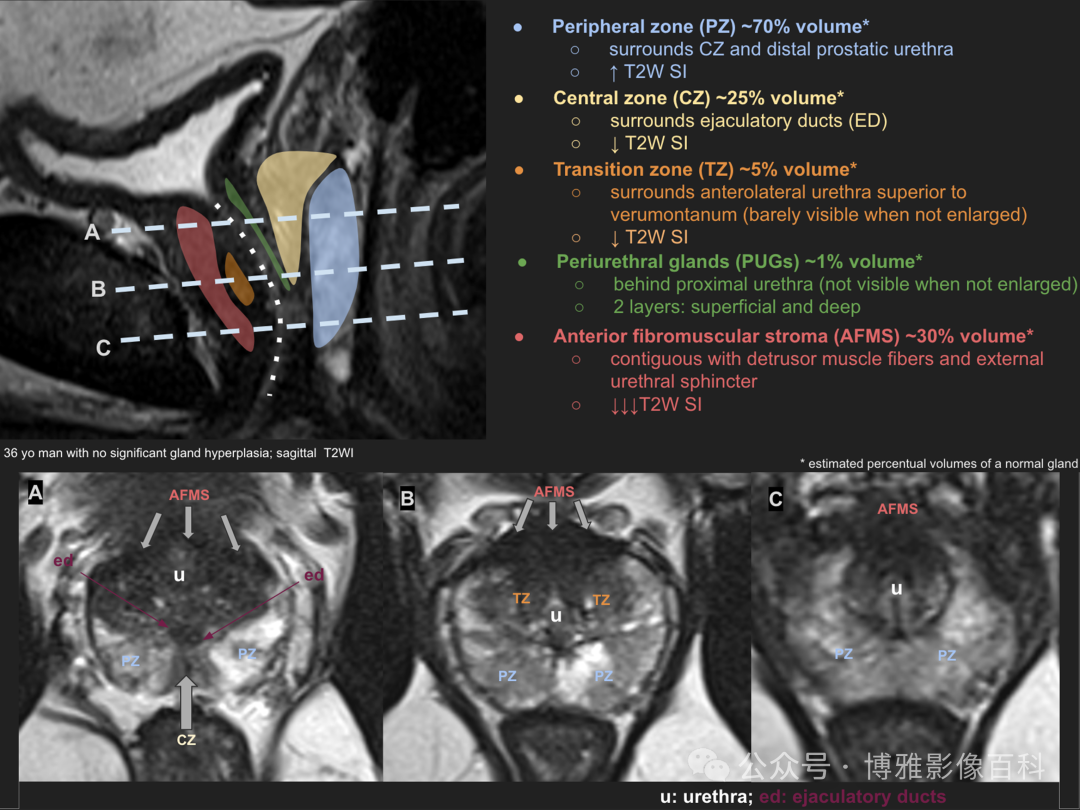

前列腺分区解剖学

70-75% 的前列腺癌起源于外周带 (PZ)。该区域的后部可以通过直肠指检进行检查。

25% 的前列腺癌起源于移行带 (TZ)。极少数前列腺癌出现在中央带或前纤维肌基质中。

MR 解剖学